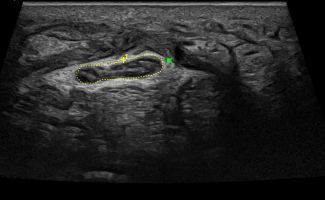

- Focal Lesions (tumors, neuromas)